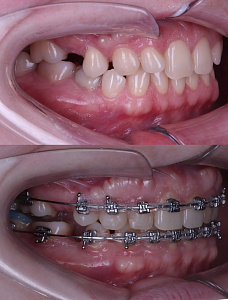

Бухарова Елена

Врач-ортодонт

- И так, друзья. Раскрываю все тайны кейса Анастасии. Она любезно согласилась, чтобы я все показала

- После диагностики стало понятно, что все не так просто, что асимметрия улыбки и несовпадение центральных линий это комплекс зубных перемещений и функционального смещения нижней челюсти, то есть она вынужденно занимает такое положение.

Это отражается и на лице: асимметрия губ и улыбки. В полости рта скученность, наклоны зубов, асимметричное смыкание справа и слева, зубы расположены на разной высоте. - А дальше она прошла все мои экзекуции: накладки, винты, цепочки, резиночки. Стойко все выдержав, Анастасия получила красивую улыбку, ровные зубные ряды, правильное смыкание челюстей и более симметричные черты лица.